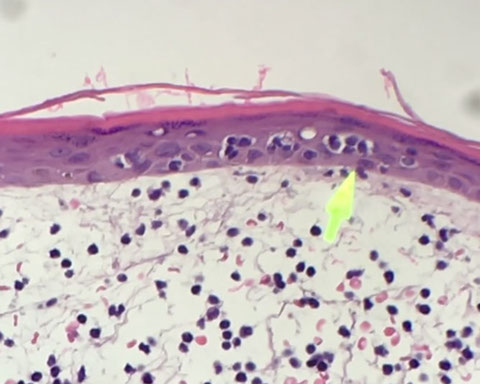

IHC of B-lymphoblastic lymphoma in LN, with TdT+ lymphoblasts surrounding negative follicle, they are positive for CD79a and PAX5, but negative for CD20.